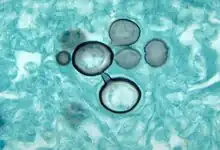

| Paracoccidioides histopathology | |

More than 90% of cases can be diagnosed with a direct histological examination of tissue, such as sputum, bronchial lavage fluid, exudates, and biopsies. Histopathological study with Gomori methenamine silver (GMS) stain or hematoxylin and eosin (H&E) stain revealing large yeast cells with translucent cell walls with multiple buds.[14]